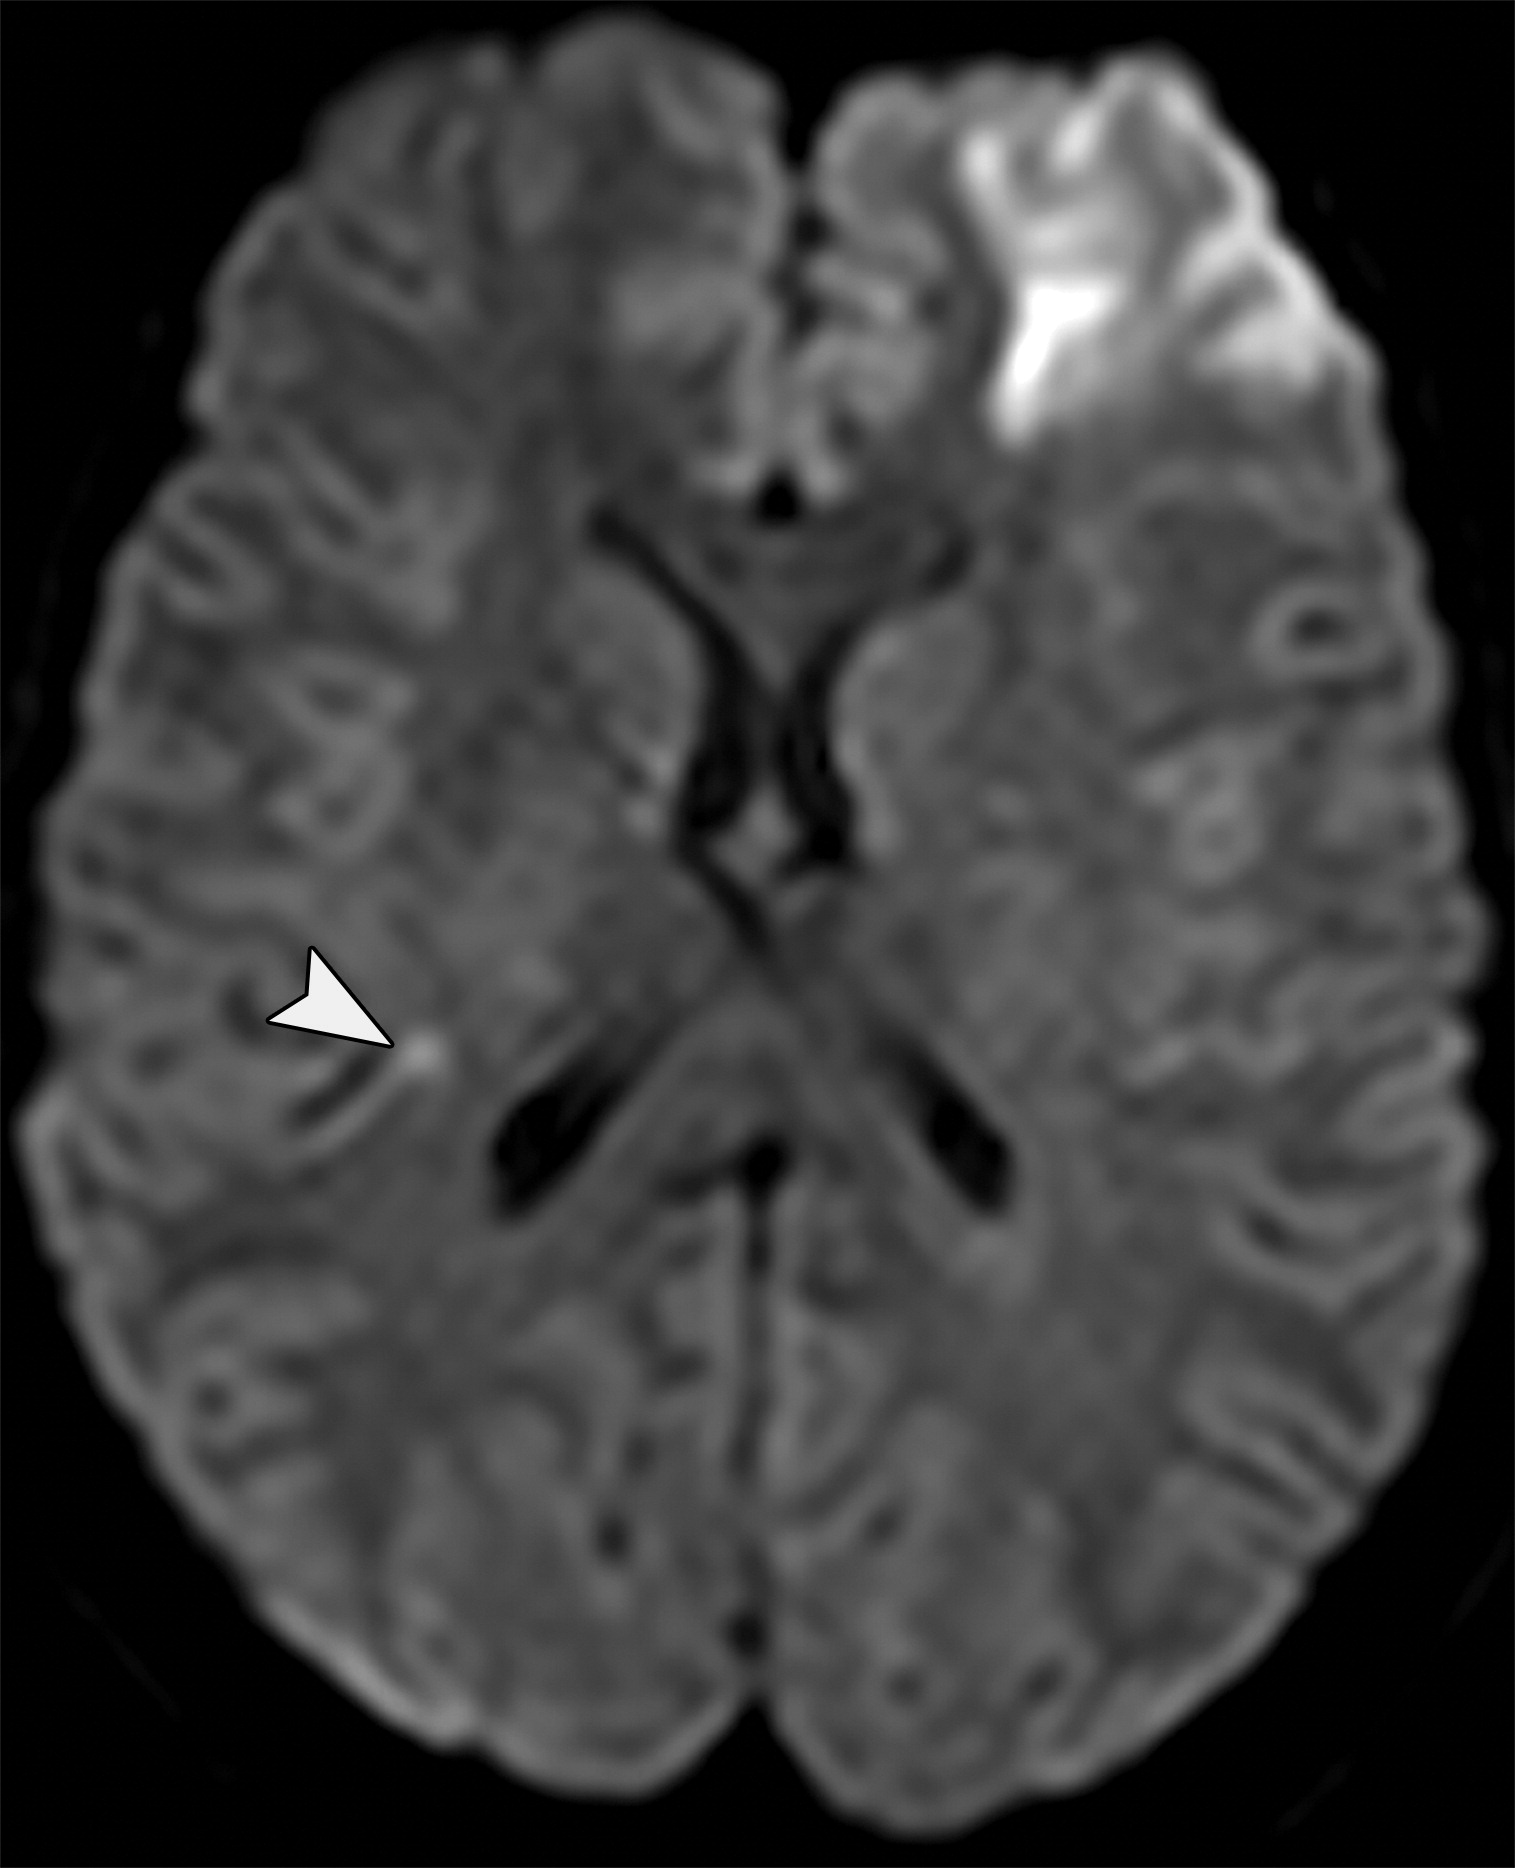

13f0c419b13c075af8c7957aee746573.jpeg

颅外脑疝。左侧额叶的急性梗死,注意右侧小灶状病变(白色短箭头)。数天后,患者出现血管源性脑水肿,并进行了去骨瓣减压术。

811f47e33d6b1d13943a77f716f35d33.jpeg

颅外脑疝。去骨瓣减压术后,脑实质从左侧额颞部缺损的位置疝出(白色长箭头)。大脑侧裂增大,左侧侧脑室的额角及枕角回缩。